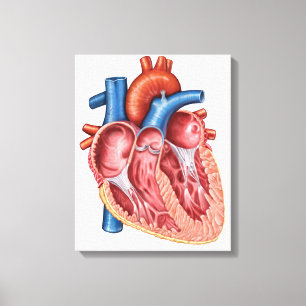

Lienzo Imagen de la radiografía de órganos internos con

Precio 218,00 €